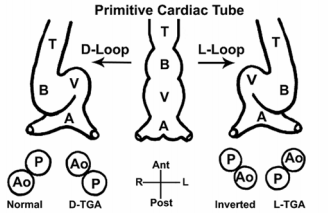

Transposition des Grands Vaisseaux (TGV)

Types Regarder l’orientation des valves aortiques et pulmoniares

- D-Type (la plus fréquente): valve aortique à droite

- L-Type (TGV “corrigée”): valve aortique à gauche